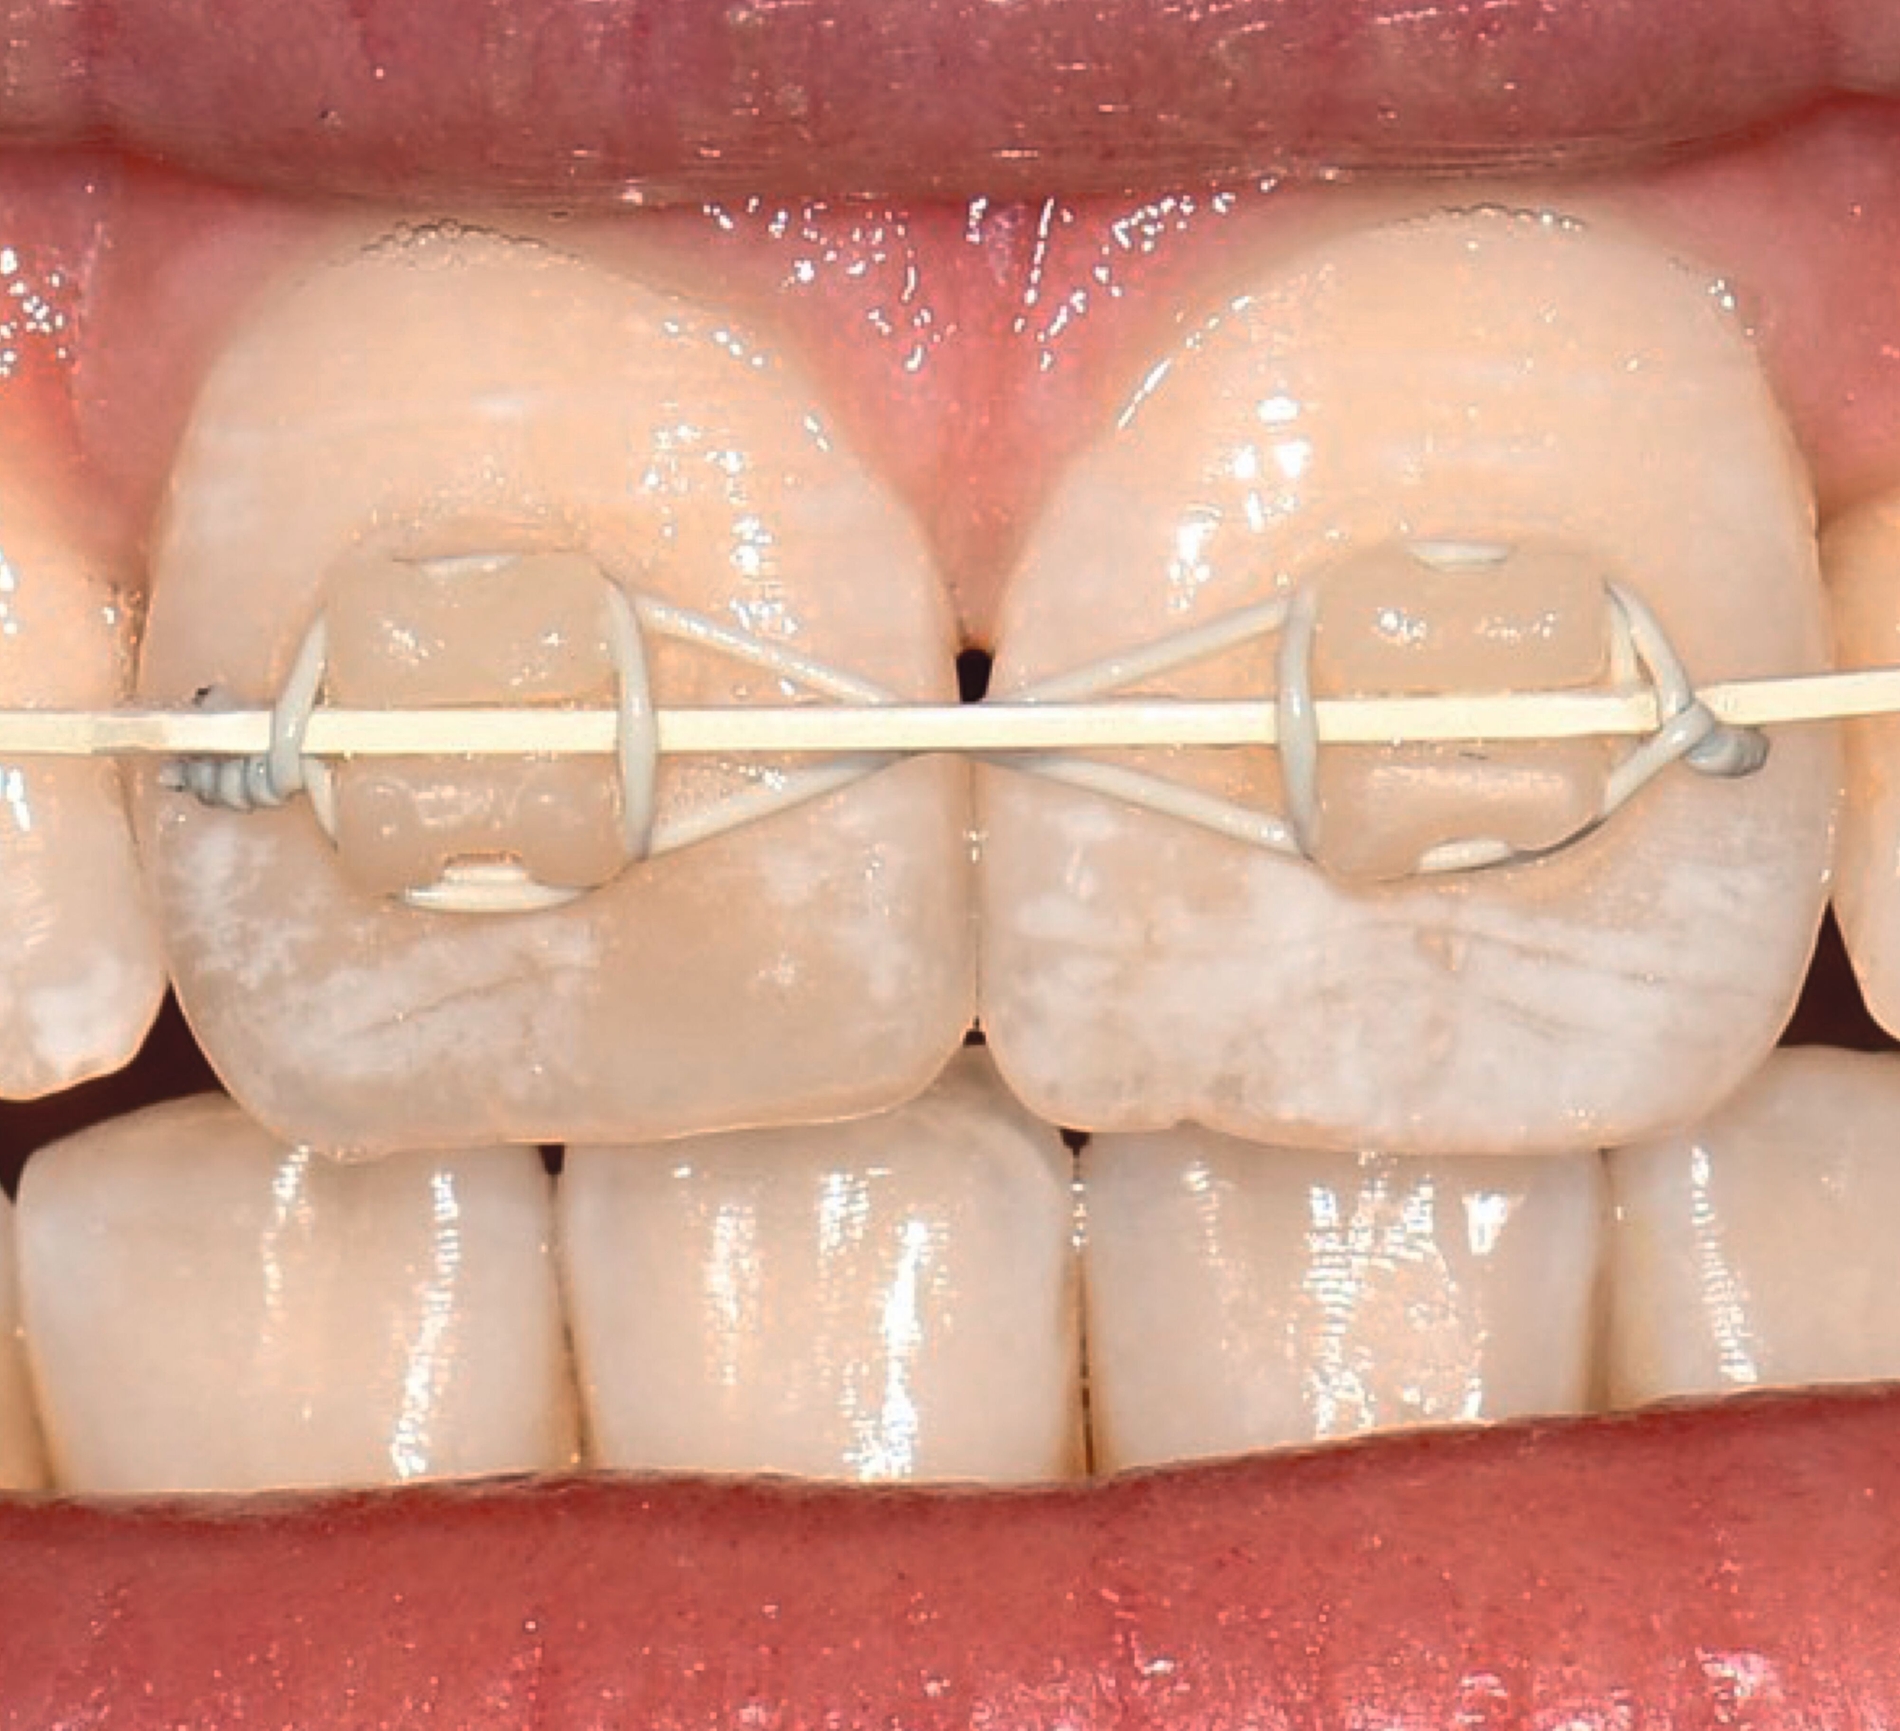

Multibracketapparatur

Als Alternative zu Alignern können auch Brackets mittlerweile im 3-D-Druckverfahren hergestellt werden [Sha et al., 2018; Sha et al., 2019; Bauer et al., 2023] (Abbildungen 2a und 2b). Neben der Nutzung des Angebots kommerzieller Anbieter (beispielsweise Lightforce Company) besteht dabei die Möglichkeit der Herstellung im praxisinternen 3-D-Drucker. Zum Einsatz eignen sich unter anderem Keramik-gefüllte 3-D-Druckkunststoffe der Biokompatibilitätsklasse IIa, die für einen langfristigen intraoralen Einsatz zertifiziert sind (zum Beispiel Permanent Crown Resin, Formlabs) [Papageorgiou et al., 2022; Bauer et al., 2023; Hodecker et al., 2023; Panayi, 2023].

Die Vorteile bestehen vordergründig in einem individualisierten Design, das die jeweiligen Therapieanforderungen berücksichtigt. Bisherige Forschungsarbeiten zeigen eine mit konventionellen Metallbrackets vergleichbare Präzision [Bauer et al., 2023], so dass eine korrekte Übertragung kieferorthopädischer Kräfte gewährleistet ist. Der Haftverbund zeigt sich gegenüber konventionellen Metallbrackets noch etwas schwächer [Hodecker et al., 2023]. Durch weitere Entwicklungen im Bereich der Bracketbasis dürfte diese Limitation jedoch adressiert werden können.

Auch die Herstellung zusätzlicher Elemente, wie beispielsweise Transpalatinalbögen aus Keramik-gefüllten 3-D-Druckkunststoffen, ist möglich (Abbildung 2c) [Thurzo et al., 2022], muss jedoch in großangelegten Studien noch auf eine ausreichende klinische Suffizienz untersucht werden. Weiter bieten 3-D-gedruckte Transferguides die Möglichkeit des „Indirekten Klebens“ [Deahl et al., 2007; Bozelli et al., 2013; Li et al., 2019; Sabbagh et al., 2022], wobei die Bracketpositionierung bereits vor dem Einsatz digital festgelegt und schließlich durch den Transferguide intraoral übertragen wird (Abbildung 2d). Neben einer verkürzten Stuhlzeit erlaubt dieses Verfahren eine besonders hohe Genauigkeit der Bracketpositionierung.